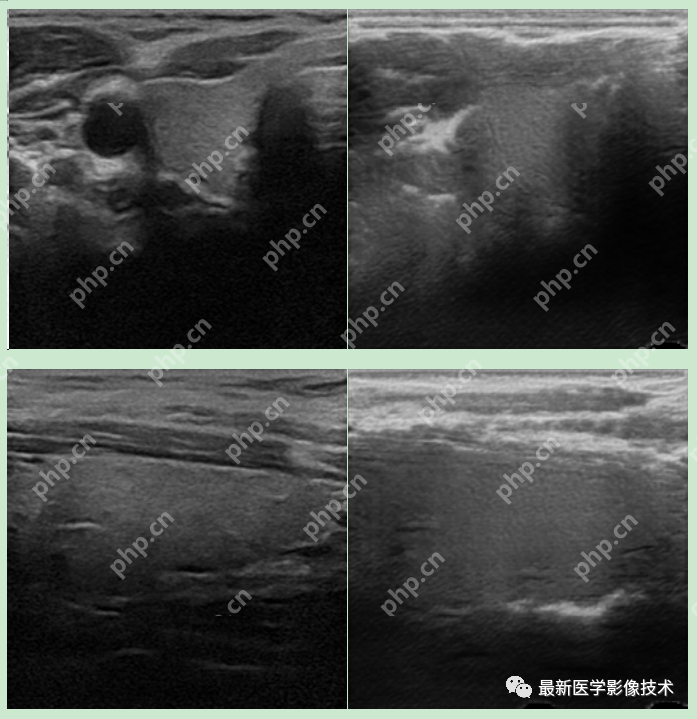

5、验证集部分生成结果

左图为低质量图像,中间为生成的高质量图像,右图为真实的高质量图像。